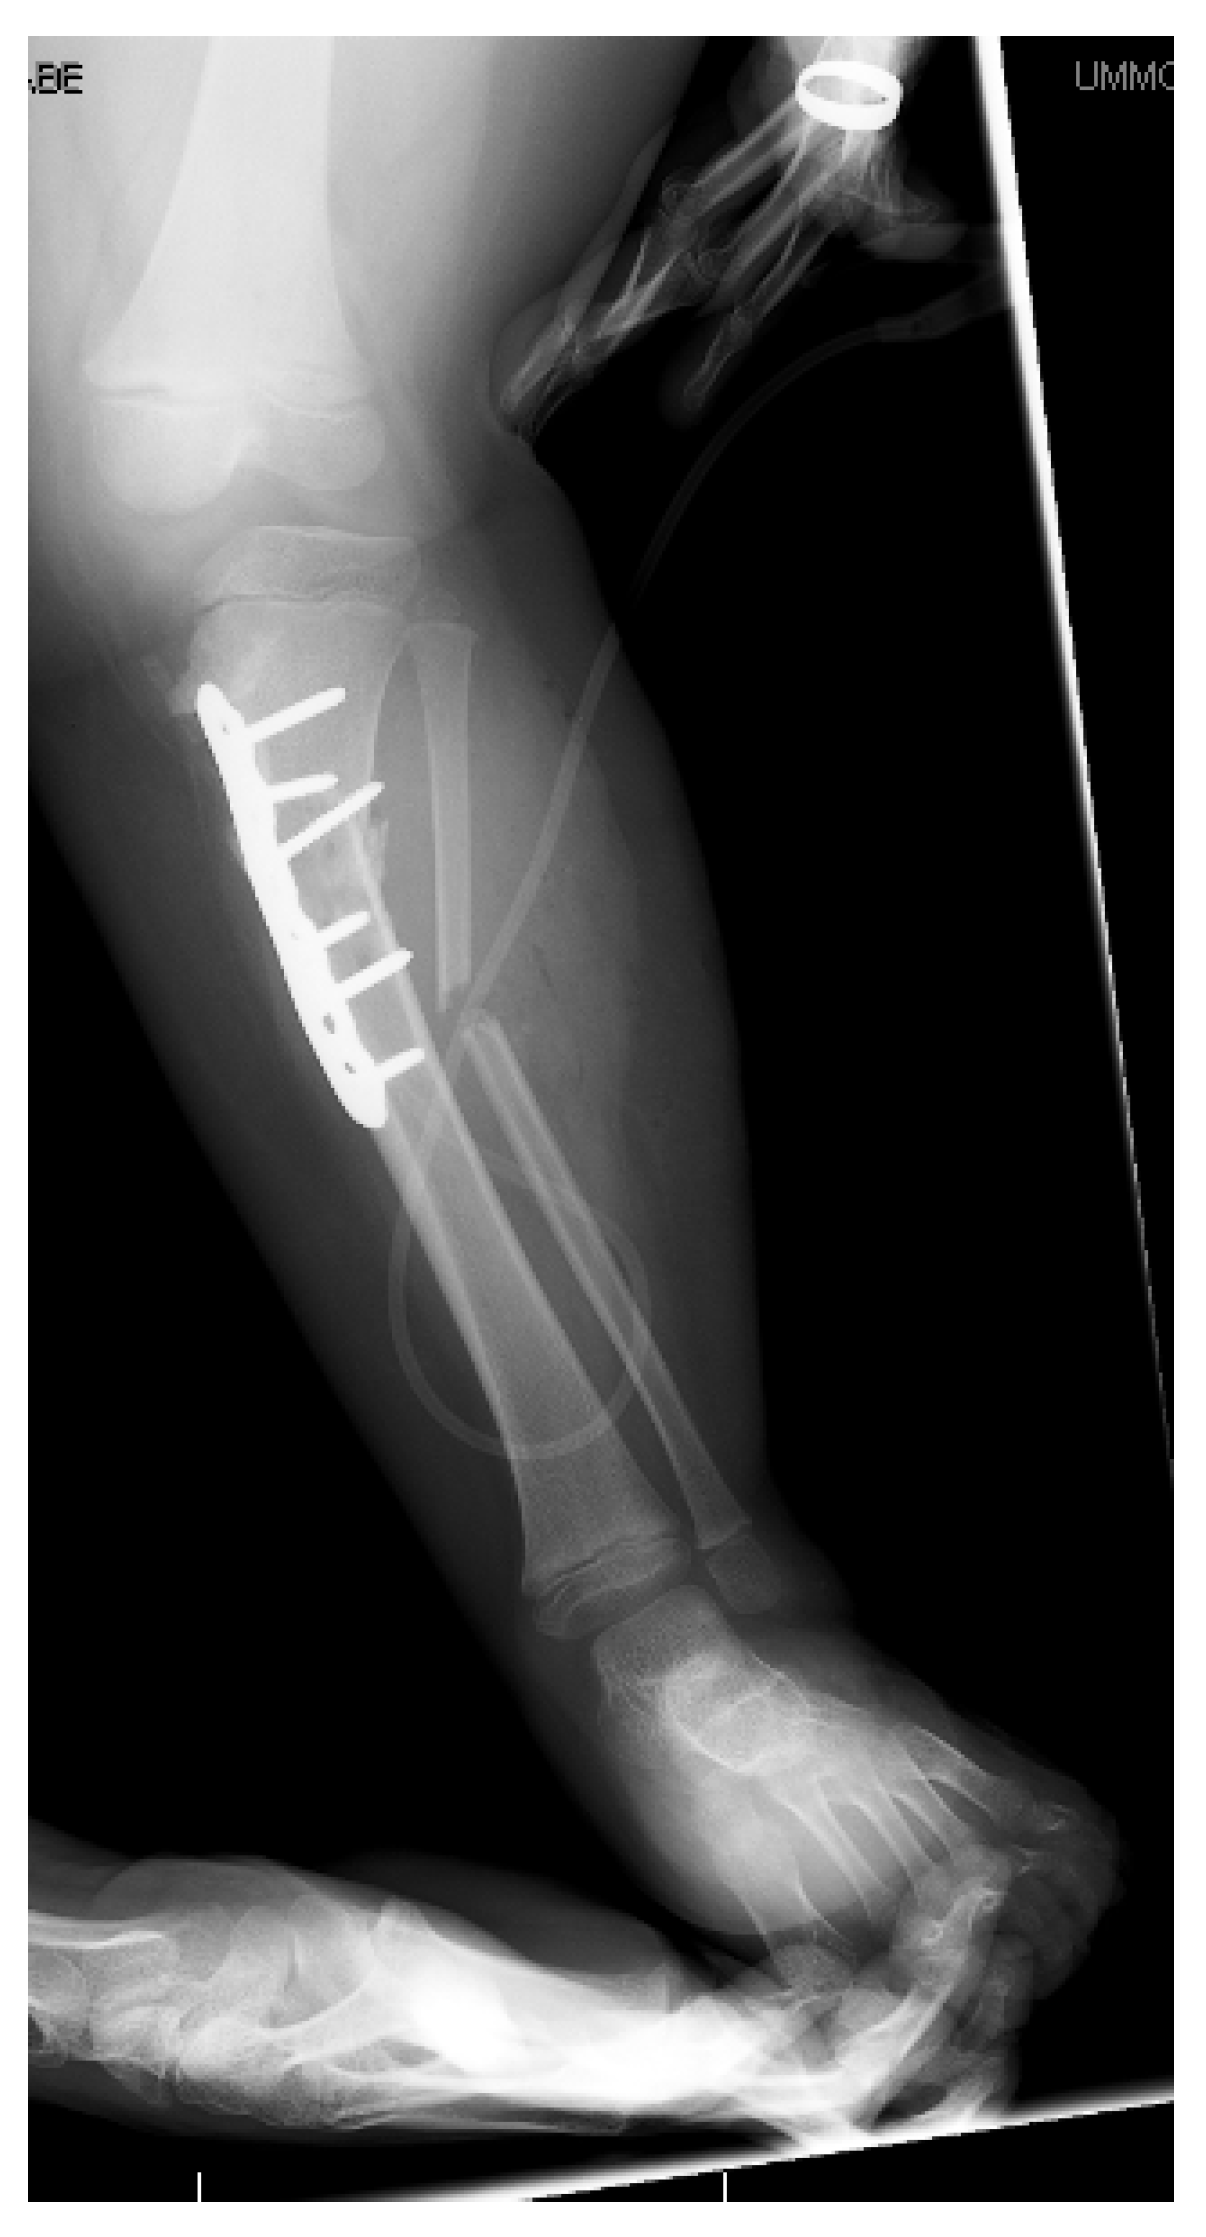

12. Physeal Arrest Resection

13. Osteotomies with Acute Correction

14. Hemi-Plateau Elevation Osteotomy

15. Combined Osteotomies